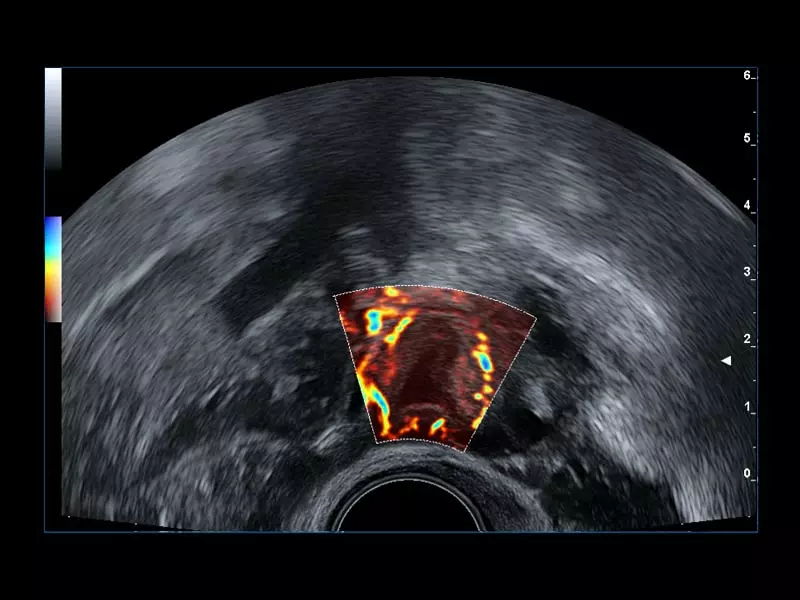

MyLab™9 Platform - Prostate contrast enhanced imaging (CnTI™)

MyLab™9 Platform - Prostate contrast enhanced imaging (CnTI™)